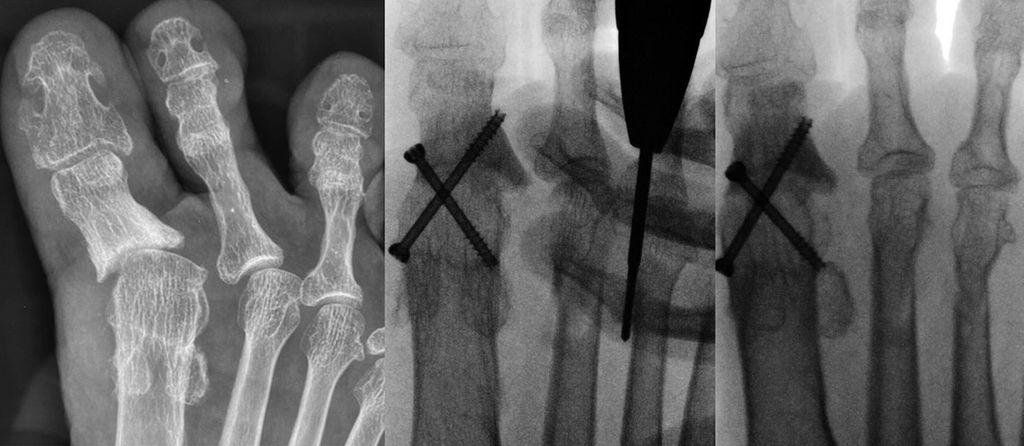

Unter der Generation 3 werden Modifikationen der Chevron-Osteotomie zusammengefasst, die per Stichinzision mittels Fräse durchgeführt werden. Fixiert wird mit kopflosen Schrauben. Redfern und Vernois bevorzugen hier sehr lange 3,5 mm- bzw. 4,0 mm-Schrauben, die von proximal medial am Metatarsale 1 in das Köpfchen eingebracht werden.2 Gerhard Kaufmann führt ebenfalls eine Osteotomie mit Fräse durch, fixiert aber weiter distal ähnlich wie bei der klassischen Chevron-Osteotomie (Abb. 1).

Vernois und Redfern präsentierten 100 Füße mit einem von 95% der Patienten als sehr gut und gut beurteilten Outcome.2 Gerhard Kaufmann publizierte 2020 seine Ergebnisse der minimalinvasiven Chevron-Osteotomie im Vergleich zur offenen Chevron-Osteotomie,6 mit Kontrollen nach 6 und 12 Wochen sowie 9Monaten und 5Jahren. Es gab keine Korrekturverluste zwischen den kurzfristigen und langfristigen Kontrollen, der Vergleich der Gruppen ergab keine Unterschiede. Jowett und Bedi analysierten 2017 die Lernkurve der minimalinvasiven Chevron-Osteotomie.7 Sie stellten eine steile Lernkurve fest. Palmanovich beschrieb 27 Patienten als notwendig, um die Lernkurve zu verlassen.8 Wenn die Technik beherrscht wird, so sind auch schwere Hallux-valgus-Fehlstellungen korrigierbar und vor allem Wundkomplikationen sind selten.